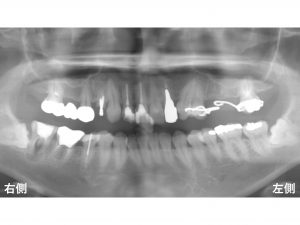

以下は治療開始前です。

上顎左側の奥歯が2歯欠損しており、

現在は義歯(入れ歯)を使用している患者様です。

また下顎右側一番奥歯にも問題があります。

歯の根が折れている状態です。

この下顎右側一番奥歯は、抜歯となってしまいます。